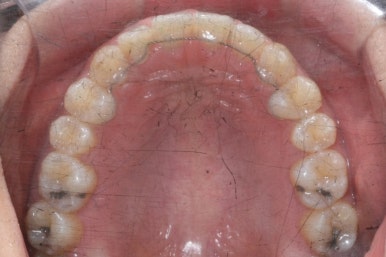

부산치아교정치과에서 치료한 이 사이가 벌어진 틈새교정을 마무리 했을 때의 모습을 보여드리겠습니다.

몰라보게 바뀌었습니다.

틈새가 다 모였고 다시 틈이 벌어지지 말라고 앞니 안쪽에는 유지장치를 달고 마무리를 했습니다.

전후를 비교해 보겠습니다.

부산치아교정치과 전후 모습입니다.

변화가 놀랍습니다.